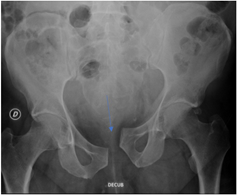

X-Ray image of an ‘open book’ pelvic injury. Note the wide separation of the pubic symphysis and the widening of the left sacroiliac joint compared to the right.